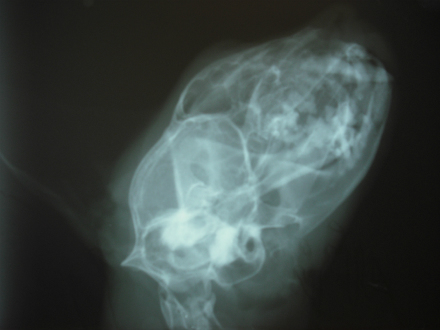

Radiografías

La radiología es una herramienta diagnóstica muy utilizada en veterinaria, al igual que en humanos. Se usa para el diagnóstico de enfermedades que afectan a los huesos como fracturas, artrosis, etc, pero también es utilizada para el examen de cavidades como tórax y abdomen. Se realiza con un aparato perfectamente homologado para tal fin, con las medidas de seguridad que ello requiere.